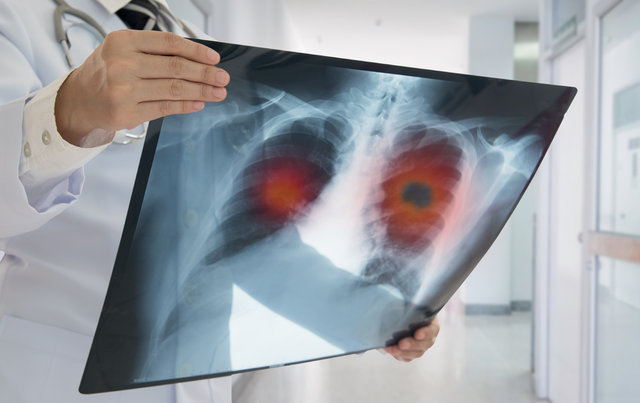

Akciğerlerin her ikisinin ya da birinin dokusunda, anormal hücrelerin kontrolsüz büyümeleri ve çoğalması ile gelişen kötü huylu tümörler, akciğer kanseri tablosunu ortaya çıkarır. Akciğer kanserinde yaş önemli bir faktördür.

Yaş ilerledikçe görülme sıklığı artar. Akciğer kanseri, 45 yaş altında nadiren ortaya çıkabilirken, genellikle 50-70 yaşlarında tanı konulur. Akciğer kanserinin kadınlarda görülme sıklığı ise giderek artar bir konumda...

ERKEN EVREDE BAŞARI İLE TEDAVİ EDİLİYOR

Akciğer kanserinin belirtileriyle karşılaşıldığında mutlaka doktora başvurulmalıdır. Ayrıntılı muayene, aile öyküsünün alınması ve uygun tetkiklerle tanı konulabilir. Akciğer kanseri erken evrelerde tespit edildiğinde başarıyla tedavi edilebiliyor.

15

Akciğer kanserinde tedavi şekli; kanserin tipi, tümörün büyüklüğü, yerleşimi, yaygınlığı ve hastanın genel durumuna göre belirlenir. Günümüzde modern tedavi yöntemleri sayesinde hastaların yaşam kalitesi ve süresi artmış durumdadır.